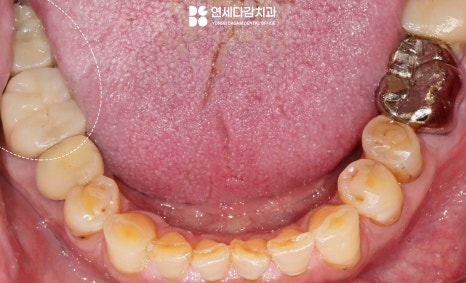

또한 저작력이 강한 특징을 가진 경우

구강 전체를 살펴봤을 때 전반적으로

치아 마모가 진행되어

치아 표면이 평평하게 닳아있는 모습을

보일 때가 많습니다.

안정적인 교합이 중요한 이유

음식을 먹을 때 저작하는 힘이 강하고

교모가 심한 경우에는 임플란트 보철을

특히 정밀하게 맞춰야 됩니다.

저작할 때 간섭이 있거나 높으면

결국 보철물이 망가지고 증상을

유발할 수 있기 때문이죠.

교합조정을 통해 균형을 맞추고

1주일 뒤 재방문하여 적응 상태를

다시 확인하는 과정이 필요합니다.